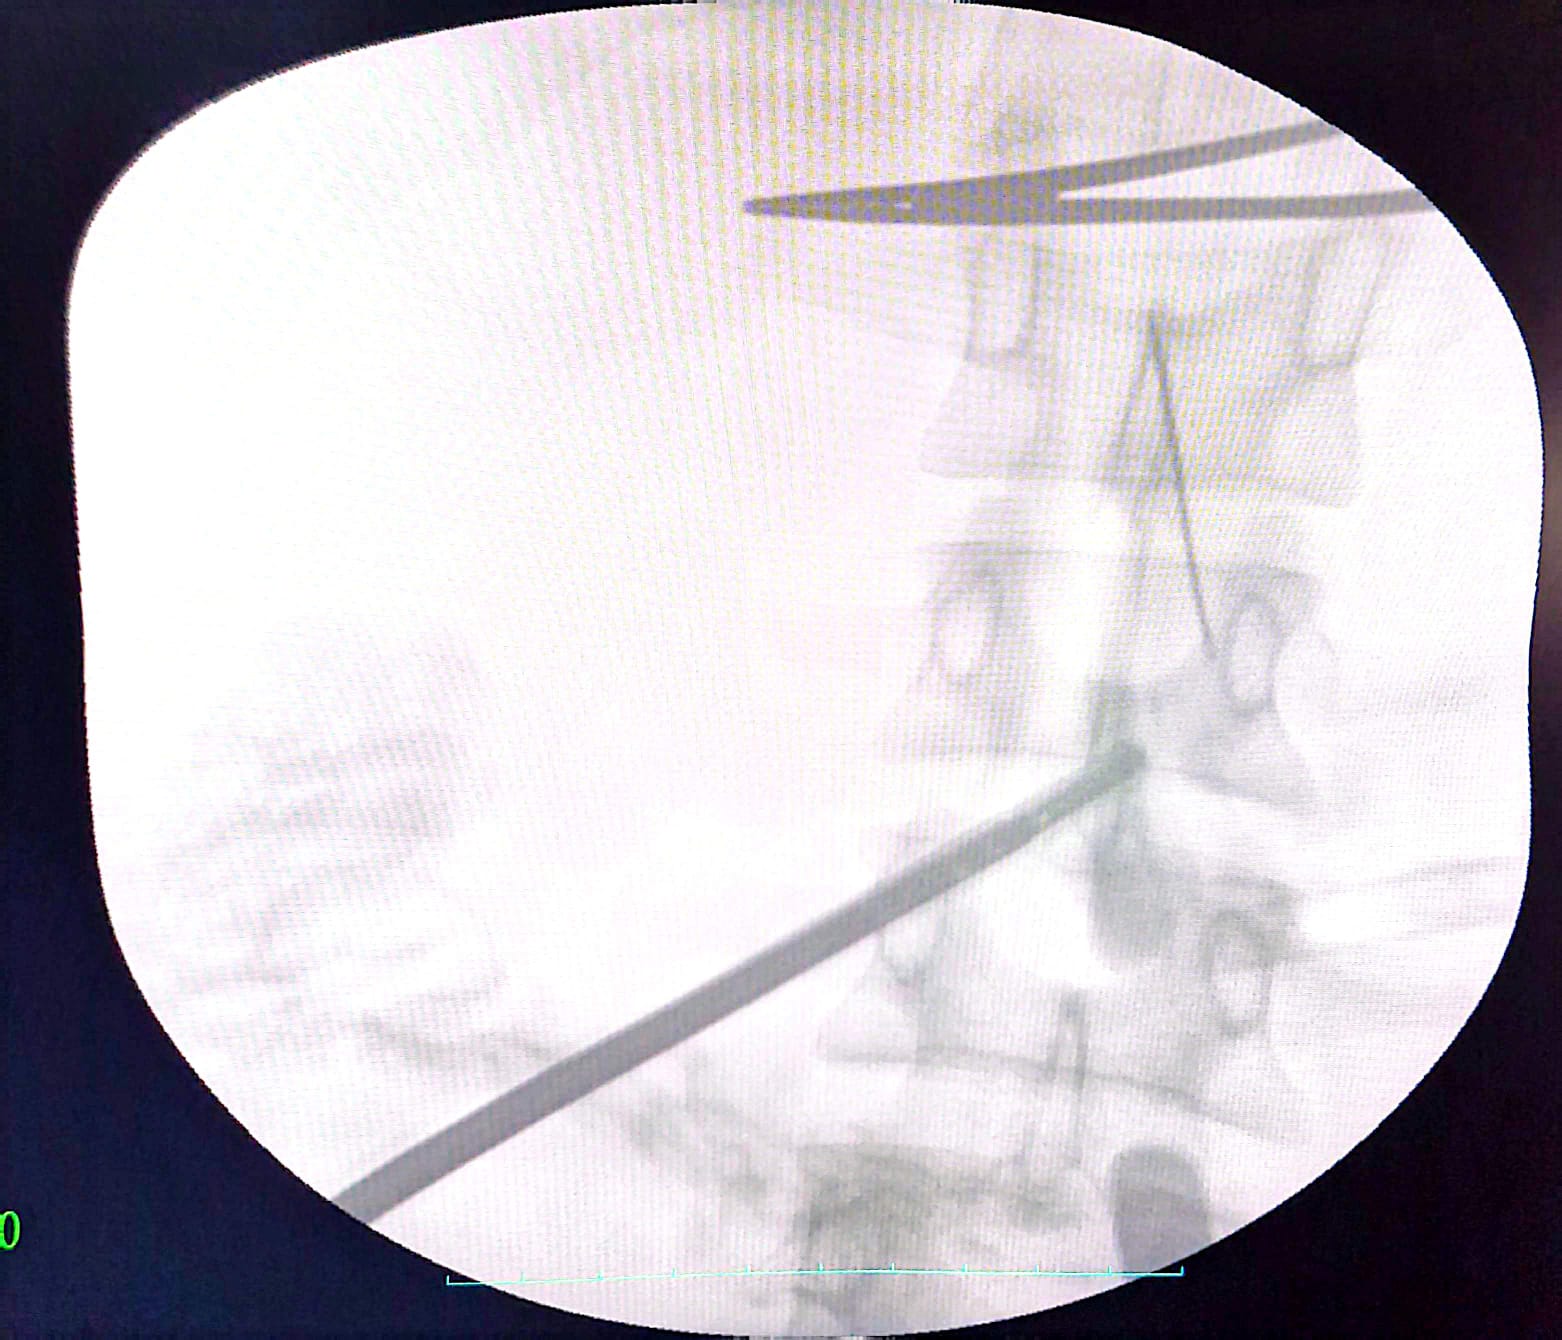

كان المستشفى الرئيسي قد استقبل فتاة تبلغ من العمر ٣٠ عاما، تعاني من آلام حادة ومزمنة بالبطن، ومن خلال تقصي التاريخ المرضي، تبين أنها ابتلعت إبرة خياطة عن طريق الخطأ منذ ما يقرب من ٤٠ يوماً، وعلى الفور، تم إجراء الفحوصات اللازمة والأشعة المقطعية التي أظهرت أن الإبرة لم تكتفِ باختراق جدار المعدة، بل استقرت في موقع تشريحي دقيق جداً بجوار الشريان الكبدي والوريد البابي الكبدي، ليقوم الفريق الطبي الذي ضم كل من، الدكتور محمود حسب النبي، أستاذ مساعد بقسم الجراحة، والطبيب حماده فتحي، والطبيب خالد حسان، والطبيب حسام محمود، مدرسين مساعدين بالقسم، والطبيب ماريو أيوب طبيب مقيم بالقسم، ومن قسم الأشعة التشخيصية والتدخلية، فريق طبي تحت إشراف الأستاذ الدكتور حسن مجلي، رئيس القسم، وضم كل من الدكتور حمدي إبراهيم، أستاذ مساعد بقسم الأشعة التشخيصية، والطبيب ميرنا يوسف، مدرس مساعد بالقسم، يعاونهم فريق طبي من قسم التخدير جاء تحت إشراف الأستاذة الدكتورة هالة سعد، رئيس القسم، وضم كل من الدكتور جورج مجدي، مدرس بالقسم، والطبيب أمونيوس خليل، مدرس مساعد بالقسم، كما عاونهم الأستاذة أماني أحمد، تمريض بقسم الجراحة، والأستاذ حسن علي، فني الأشعة، باستخدام جهاز الأشعة C-Arm، بدلاً من اللجوء إلى الجراحة التقليدية (فتح البطن الاستكشافي)، التي تتطلب وقتاً أطول للتعافي، لرصد مكان الإبرة بدقة متناهية.

ونجح الفريق الطبي في استخراج الإبرة بالكامل باستخدام المنظار الجراحي عبر (٣) فتحات صغيرة فقط في جدار البطن.